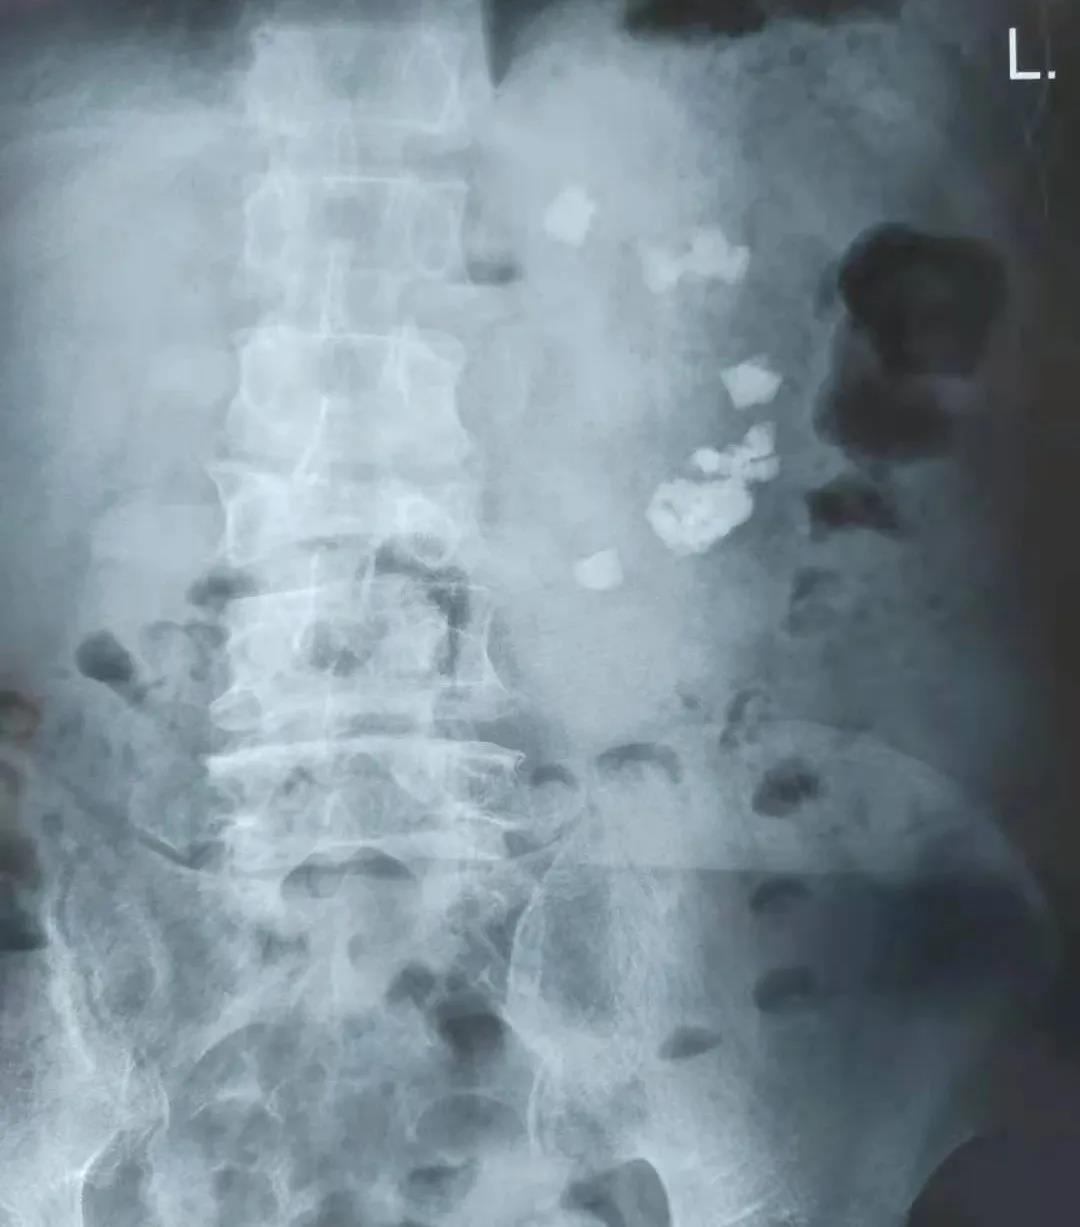

崔先生的左腎結(jié)石病史已有30多年,20余年前曾在外院進(jìn)行左腎切開取石手術(shù)治療,但是10余年前在定期查體時(shí)卻發(fā)現(xiàn)左腎結(jié)石已再次復(fù)發(fā)。出于對(duì)手術(shù)的抗拒,崔先生一直默默忍受著結(jié)石帶來的疼痛和不適,并且飽受著結(jié)石引發(fā)的反復(fù)泌尿道感染的折磨。直至最近,崔先生出現(xiàn)了左輸尿管的結(jié)石梗阻,變本加厲的疼痛使他苦不堪言。經(jīng)朋友推薦,崔先生懷著忐忑不安的心情來到了濰坊市市立醫(yī)院。經(jīng)過全面檢查,發(fā)現(xiàn)患者的左腎結(jié)石數(shù)量極多,且分布松散,幾乎上中下所有腎盞中都有結(jié)石,而且患者有開放手術(shù)史,腎臟原有的結(jié)構(gòu)已經(jīng)遭到了破壞,腎周還與周圍的腸管發(fā)生了黏連,這無疑增加了手術(shù)的難度和風(fēng)險(xiǎn)性。

患者術(shù)前腹部平片

經(jīng)過全面細(xì)致的術(shù)前準(zhǔn)備,副院長(zhǎng)、泌尿外科主任解魯明為崔先生分期實(shí)施了經(jīng)尿道輸尿管鏡左輸尿管結(jié)石碎石取石術(shù)+經(jīng)皮腎鏡左腎結(jié)石碎石取石術(shù)。在解院長(zhǎng)的妙手醫(yī)術(shù)和團(tuán)隊(duì)的默契配合下,手術(shù)十分順利,崔先生術(shù)后疼痛輕微、感覺良好,身體恢復(fù)很快,已于不久前康復(fù)出院。